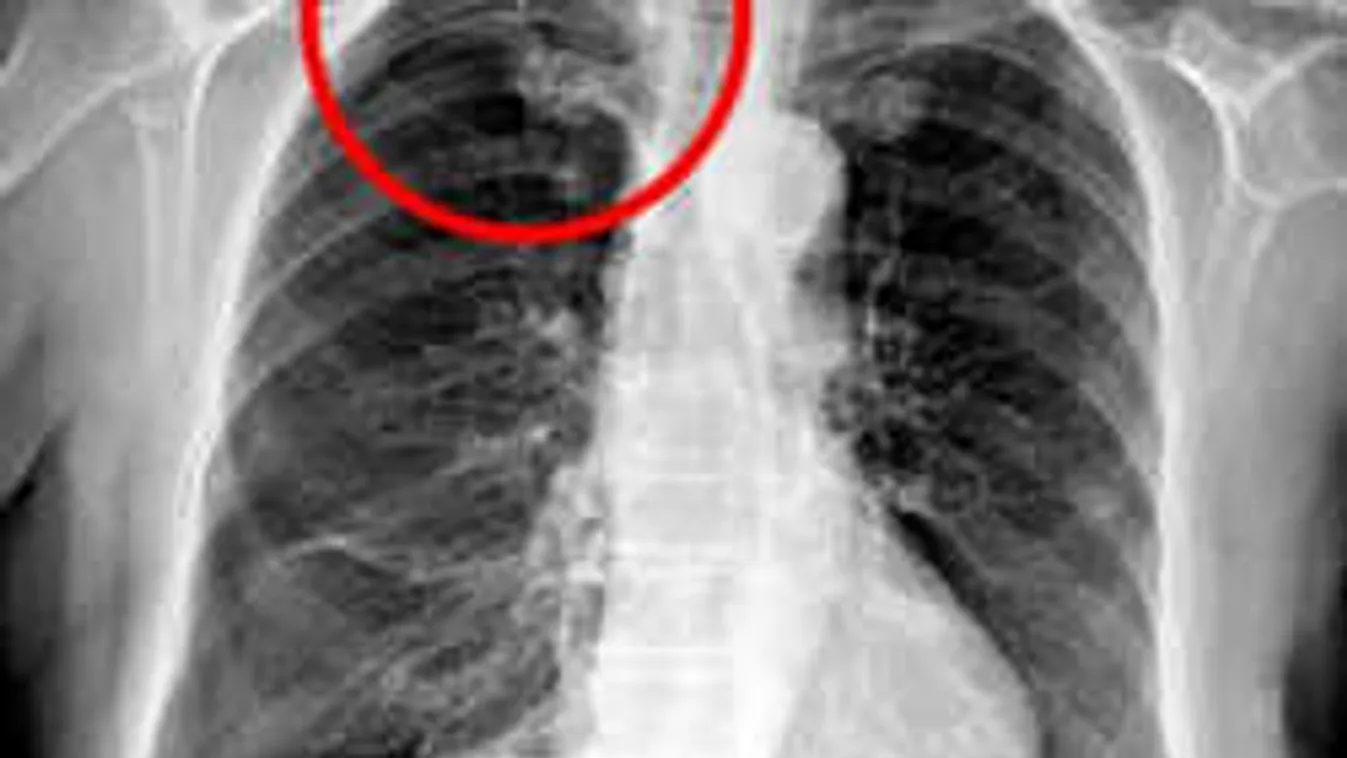

Megröntgenezték és kiderült, hogy összeomlott a jobb tüdejének egy része, légmell alakult ki nála.

A bajt az okozhatta, hogy a tűt túl mélyen, és rossz szögben szúrták be a lapockák közötti területen - írta meg a BMJ Case Reports orvosi szakfolyóirat.